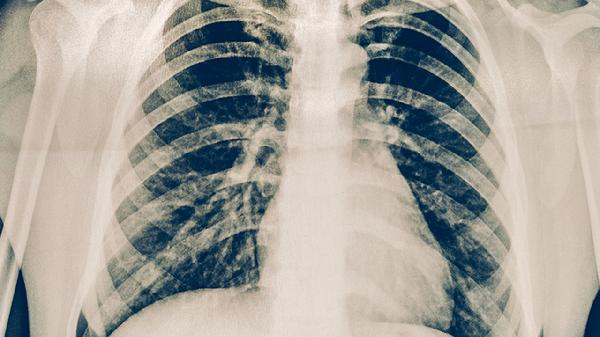

肺心病可通过氧疗、药物治疗、控制原发病、改善生活方式、手术治疗等方式治疗。肺心病通常由慢性阻塞性肺疾病、肺动脉高压、肺部感染、胸廓畸形、睡眠呼吸暂停综合征等原因引起。